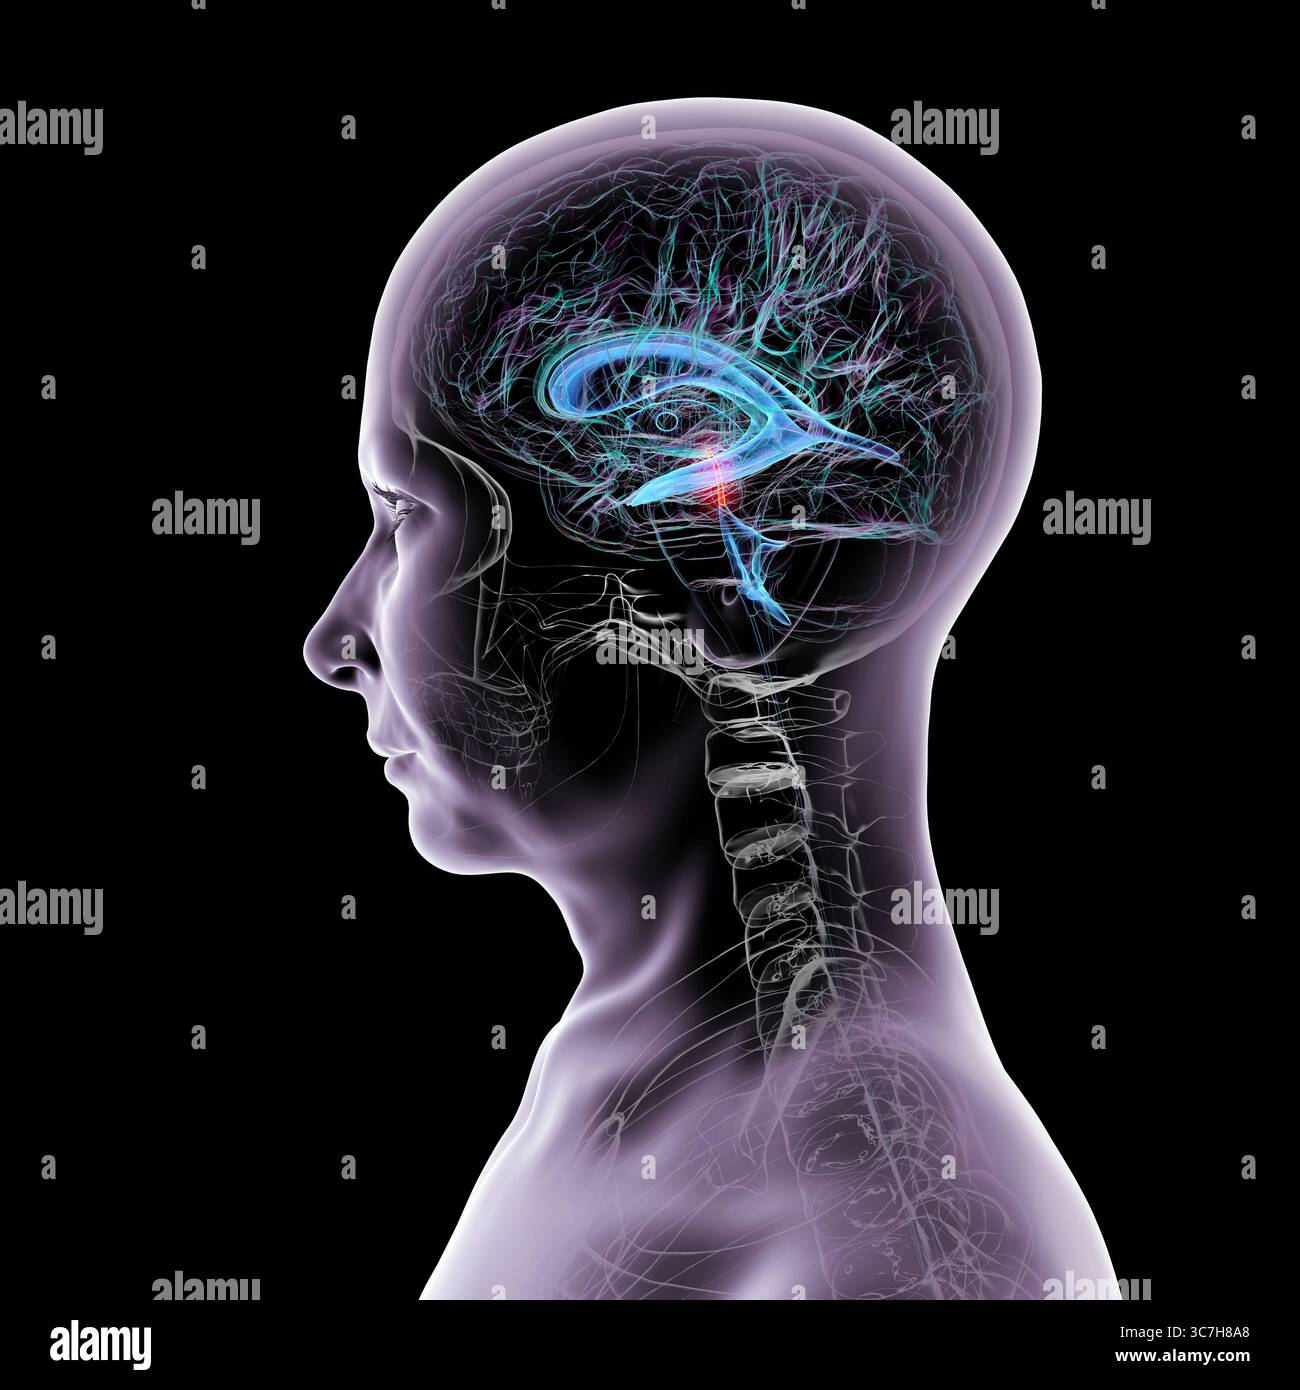

RF3C7H8A8–Abbildung des Gehirns mit hervorgehobenem Aquädukt (rot) und ventrikulärem System (blau), Darstellung des Liquorflusses.

RF3C7H8A6–Abbildung des Gehirns mit hervorgehobenem Aquädukt (rot) und ventrikulärem System (blau), Darstellung des Liquorflusses.

RF3C7H8AA–Abbildung des Gehirns mit hervorgehobenem Aquädukt (rot) und ventrikulärem System (blau), Darstellung des Liquorflusses.

RF3C7H8AF–Abbildung des Gehirns mit hervorgehobenem Aquädukt (rot) und ventrikulärem System (blau), Darstellung des Liquorflusses.

RF3C7H8A3–Abbildung des Gehirns mit hervorgehobenem Aquädukt (rot) und ventrikulärem System (blau), Darstellung des Liquorflusses.